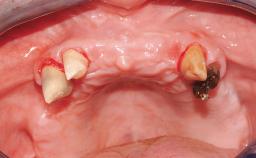

Immediate Loading of Six Implants in the Mandible and Six Implants in the Maxilla and Final Restoration with Full-Arch CAD/CAM Metal Framework FDPs Involving Digital Planning and Guided Surgery

Immediate loading of dental implants is increasingly popular with clinicians and patients. The idea of delivering a restoration directly after implant insertion,combined with a less invasive procedure (flapless protocol), has made treatment protocols involving dental implants more accessible to dentists and patients. However,immediate-loading concepts require sophisticated and exact planning. To facilitate this, conventional panoramic tomographs and periapical radiographs are often taken with the patient wearing a radiographic template simulating the preoperative prosthetic design. However, these radiographs do not provide all the necessary information. In addition, some protocols call for conventional surgical templates fabricated on the diagnostic cast. These will inform the bone drilling points and drill angles, but do not reference the underlying anatomical structures or provide exact 3-D guidance.

Defining Characteristics Fully edentulous upper jaw to be rehabilitated with four or more implants